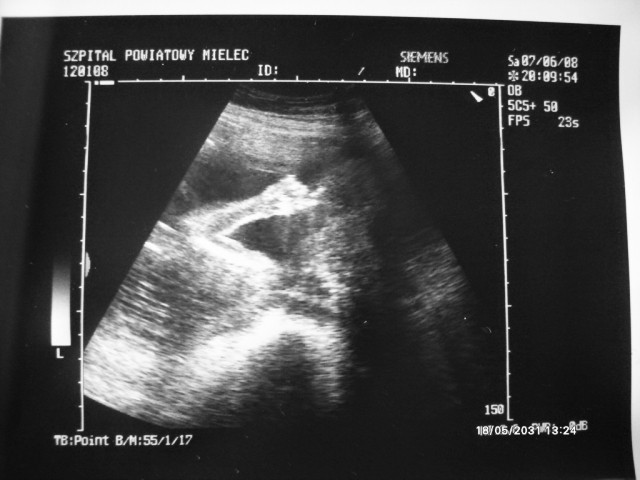

A oto moja mała:)

Załączniki

• 01USG.JPG

01USG.JPG

56,3 KB · Wyświetleń: 49

• 02USG.jpg

02USG.jpg

77,3 KB · Wyświetleń: 54

Malena śliczne zdjątka bąbelka.

Malene81 śliczne fotki jak ładnie widać mam bardzo podobne USG laury:tak: